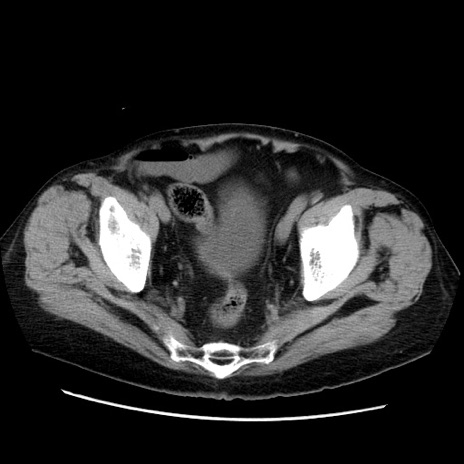

症例21(横断像)

【症例】70歳代男性

【主訴】腹痛

【現病歴】肝硬変・肝細胞癌にてかかりつけの方。約9時間前に食後より腹痛出現。症状が徐々に増悪し、嘔吐出現したため来院。

【既往歴】肝硬変、肝細胞癌(RFA、TACE後)

【身体所見】意識清明、表情苦悶様、BT 36℃、BP 129/78mmHg、P 88bpm、SpO2 97%(RA)、右上腹部から心窩部にかけて圧痛あり、反跳痛なし、筋性防御あり。

【データ】WBC 5800、CRP 0.16